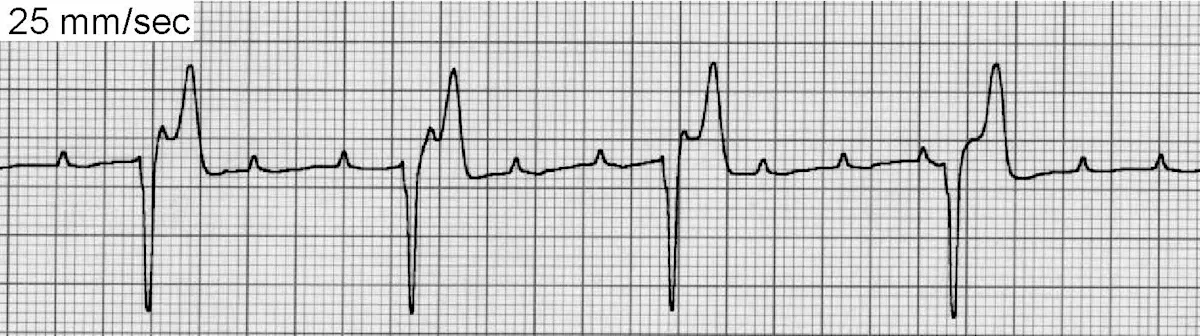

SVT (Figure 4) is an infrequent arrhythmia defined as 3 or more SV beats in succession. SVT is usually associated with significant heart disease and atrial enlargement. A unique form of SVT is associated with an accessory pathway connecting the atria and ventricles. When occurring as a paroxysm, the rhythm is fast and regular, often with abrupt onset and termination. The first heart sound is often accentuated while audible murmurs diminish in intensity during the paroxysm as a result of decreased stroke volume. SVT usually results from a reentry circuit, although it may also occur subsequent to enhanced normal or abnormal automaticity.

FIGURE 4ECG of supraventricular tachycardia

Sustained SVT can provoke loss of normal myocardial contractility and eventual heart failure, while paroxysmal SVT can cause episodic weakness and syncope. Therapeutic interventions can be administered to acutely terminate SVT and prevent recurrence.